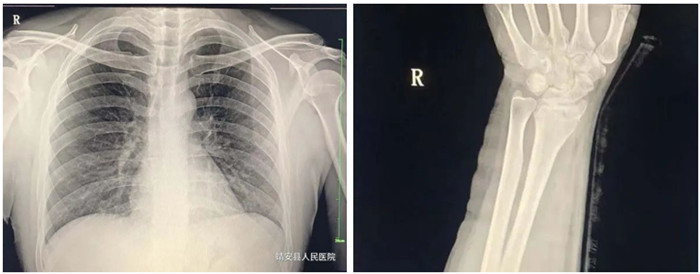

2.脊柱、四肢骨骼及關節(jié)

適應癥:骨齡檢查、先天性發(fā)育異常、骨缺血性壞死;骨質(zhì)疏松、骨髓炎、骨腫瘤、骨關節(jié)創(chuàng)傷、骨關節(jié)結核、骨關節(jié)炎性病變、軟組織病變等疾病。

3.胸部

適應癥:氣管支氣管?。ㄖ夤芙Y石及異物等);肺部病變(先天性發(fā)育異常、炎癥、結核、腫瘤等);縱膈病變(氣腫、血腫、腫瘤與囊腫等)。